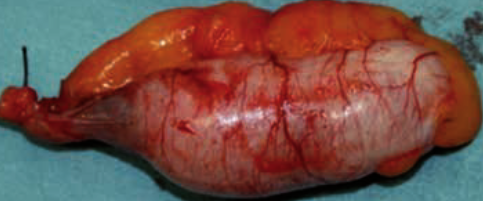

Χειρουργικά παρασκευάσματα ώριμου τερατώματος και σκωληκοειδούς (Ευγενική παραχώρηση Dr. V. Penopoulos)